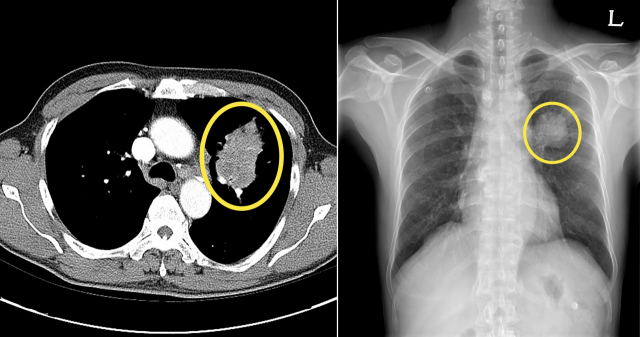

폐암 초기증상 - 10. 무증상

폐암 환자의 약 10~15%는 별다른 증상이 없을 수 있습니다. 폐암이 초기 단계를 지나 중기에 이르면 증상이 서서히 나타나는 것으로 알려져 있습니다. 그러나 이때 나타나는 증상도 폐암으로 진단하기 어려운 경미한 증상이나 다른 질환으로 오인할 수 있는 증상입니다.

폐암 초기증상 - 11. 호흡곤란

폐가 영향을 받으면 약간의 운동에도 숨이 가빠지고 호흡 곤란을 경험할 수 있습니다. 암세포의 성장으로 인한 폐 기능 상실로 인해 일부 사람들은 호흡 곤란을 겪을 수 있으며 흉막 삼출, 폐 붕괴 및 상기도 폐쇄로 인해 호흡이 어려워질 수 있습니다. 가벼운 증상을 무시하기 쉽지만 무시하면 통제할 수 없을 정도로 커질 수 있으므로 신속하게 검사를 받아야 합니다.